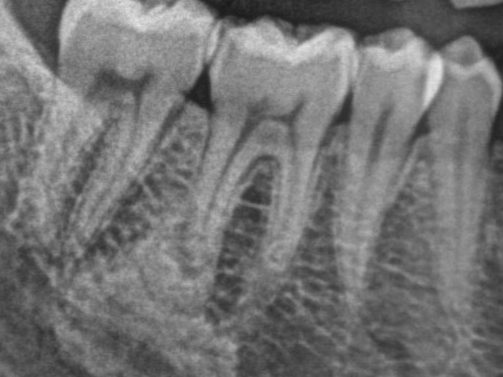

Greffes avant la pose d'implant

Pour préparer une zone avant implant ou pour renforcer les tissus de soutien.

Greffes de gencive : tissu prélevé au palais pour couvrir une racine dénudée.

Greffes osseuses : pour reconstruire l’os manquant avant implant.